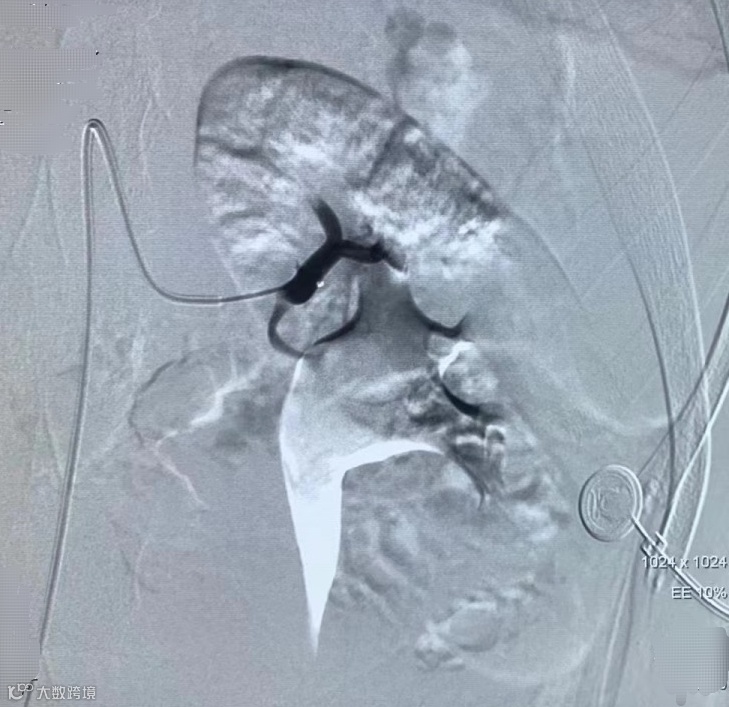

6月20日下午,张成文在刘建超医生的配合下,通过微创介入手术的方式,在患者的右大腿股骨沟动脉处进行穿刺,行肾动脉栓塞术,顺利为患者止血,成功保住了患者的肾脏。手术经历一个小时顺利完成,患者的血尿立即停止,无明显不适。